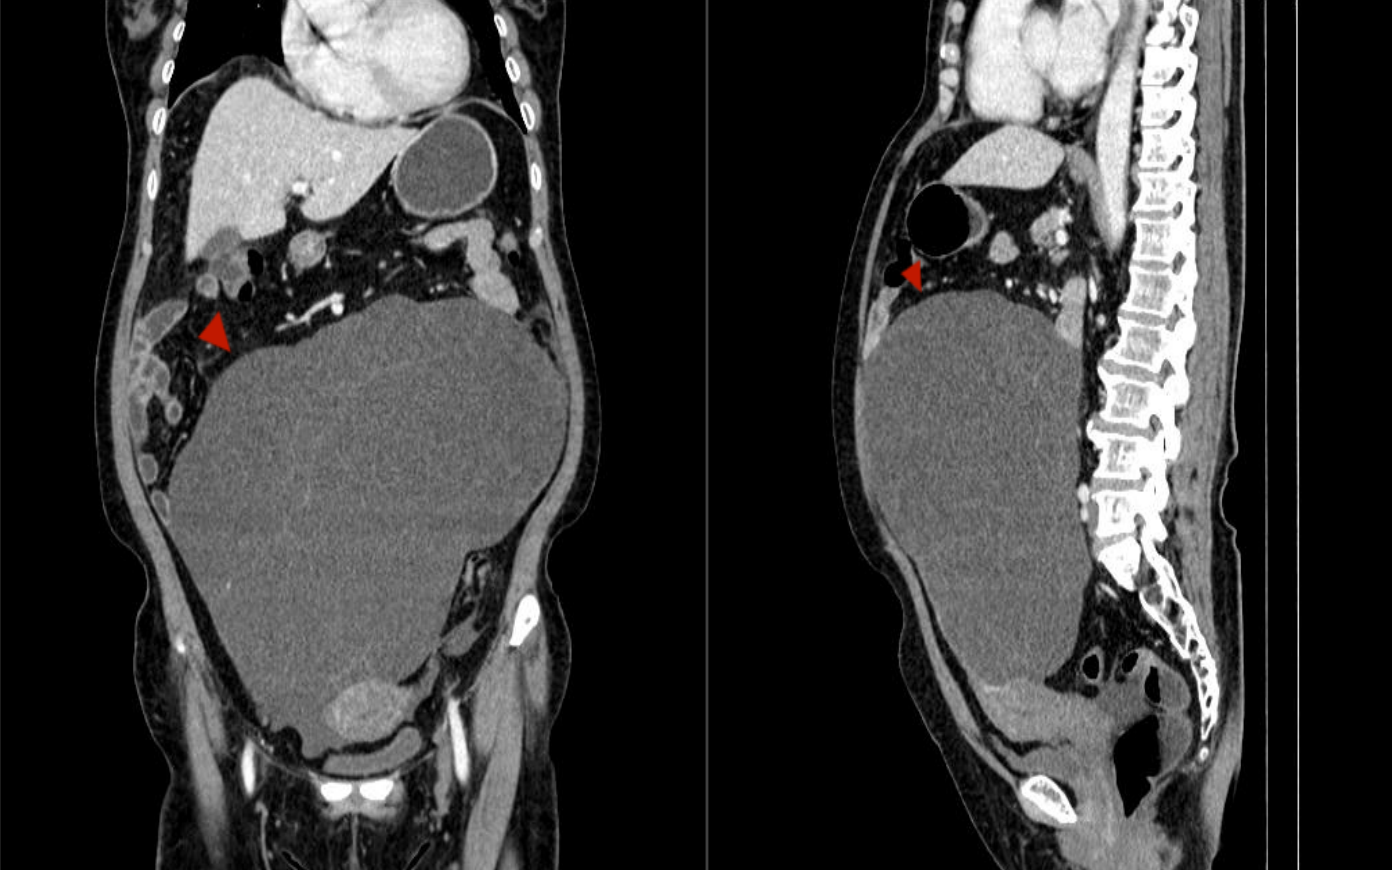

在我院妇产儿保医学中心(金山院区),医生经过详细的检查,发现林阿姨的盆腹腔里长了一个巨大的包块!

直径接近40厘米!几乎填满了整个盆腹腔,压迫着周围的器官。

如此巨大的肿瘤,也预示着手术的高风险:肿瘤剥离困难易出血、位置深在易损伤周围重要血管神经及脏器(如输尿管、肠道)、高龄患者对手术的耐受性相对较低。

妇产儿保医学中心陈政主任医师牵头组织了多学科联合会诊(MDT)。对林女士的病情进行了全面评估,并制定了详尽的手术方案和应急预案。医疗团队凭借精细的操作,成功地将这个与周围组织紧密粘连的巨大肿瘤完整切除(病理证实为来源于左侧卵巢的肿瘤)。